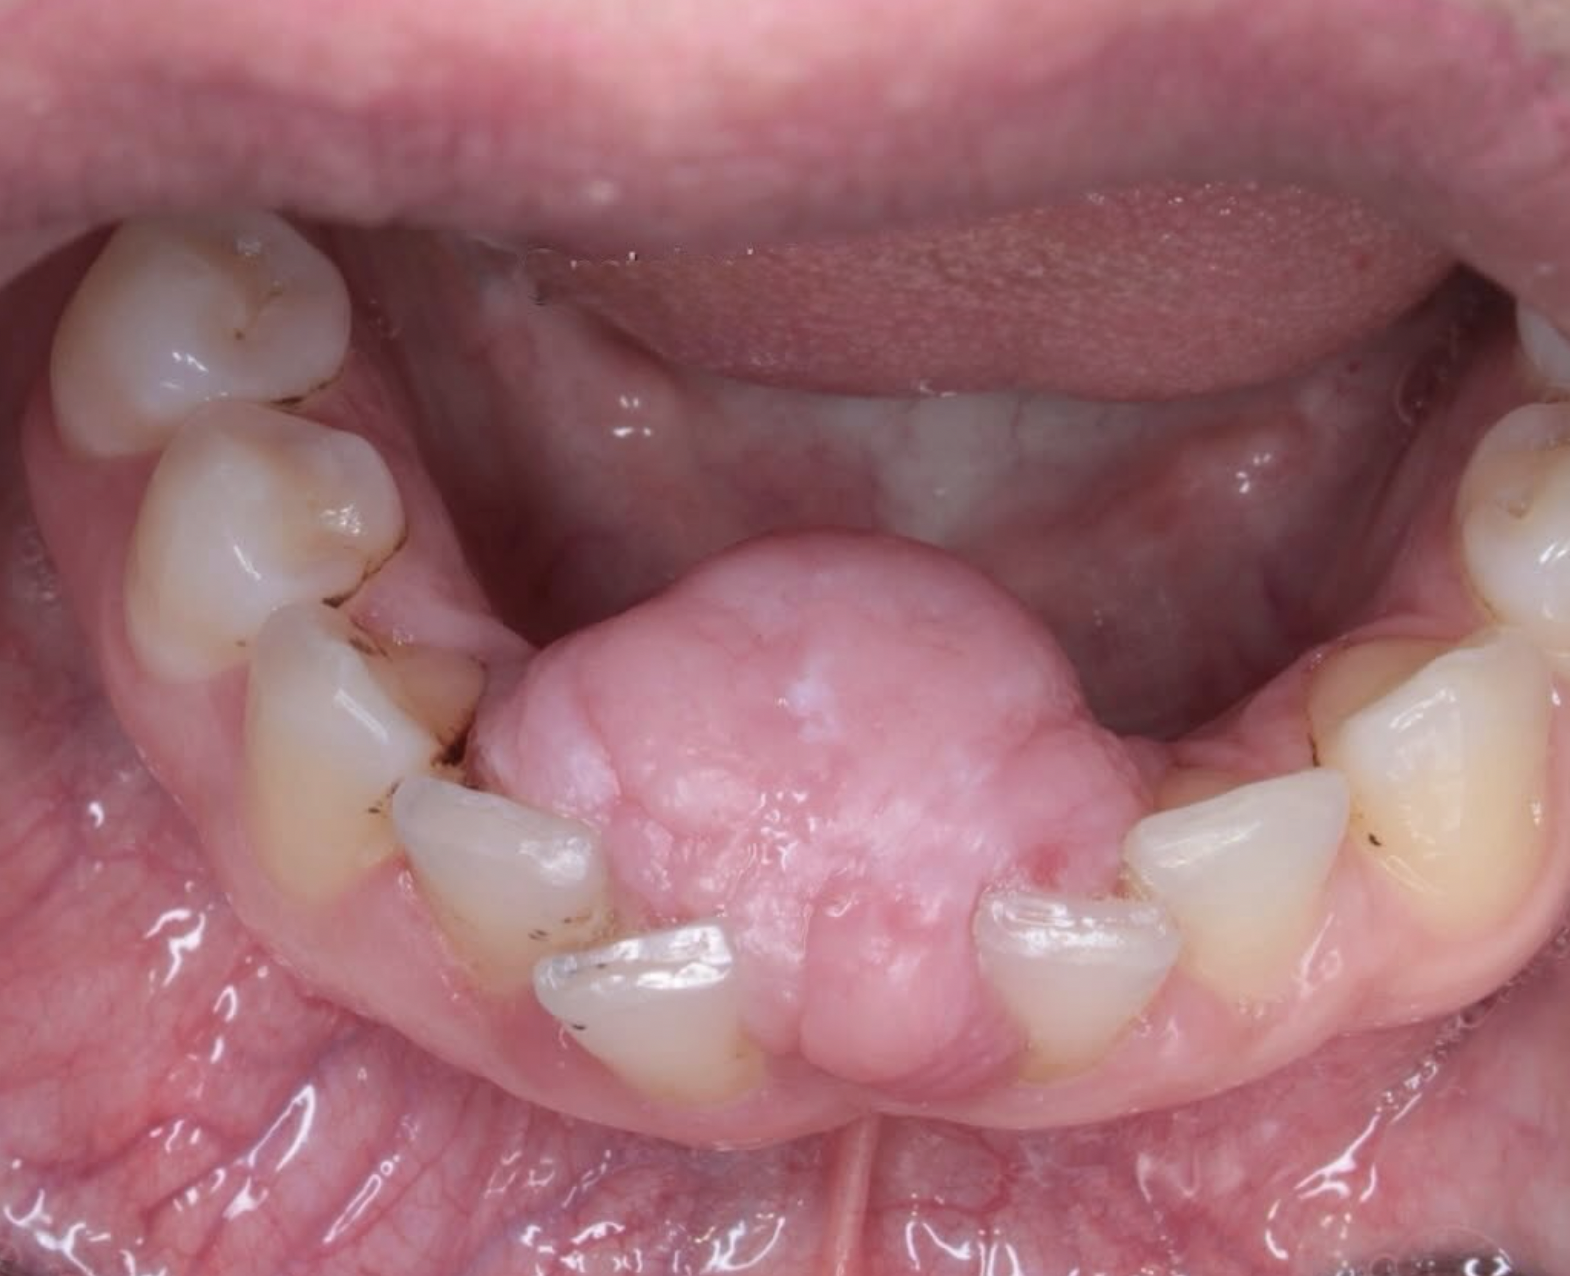

Acreditamos na importância da prática e da interação para o aprendizado significativo. Através de estudos de casos reais e atividades práticas, você aplicará seus conhecimentos em situações do cotidiano, desenvolvendo habilidades essenciais para a prática clínica.

✦ Lesões em gengiva;

✦ Granuloma piogênico;

✦ Fibroma periférico;

✦ Mucocele;

✦ Rânula;

✦ Hiperplasia Fibrosa Inflamatória

✦ Hiperplasia papilar

✦ Hiperplasia por câmara de sucção

✦ Pólipo fibroepitelial

Durante as aulas exploraremos as diferentes doenças e condições que podem afetar a cavidade oral, como cáries dentárias, gengivite, periodontite, lesões ulcerativas, lesões pré-cancerosas e câncer bucal.